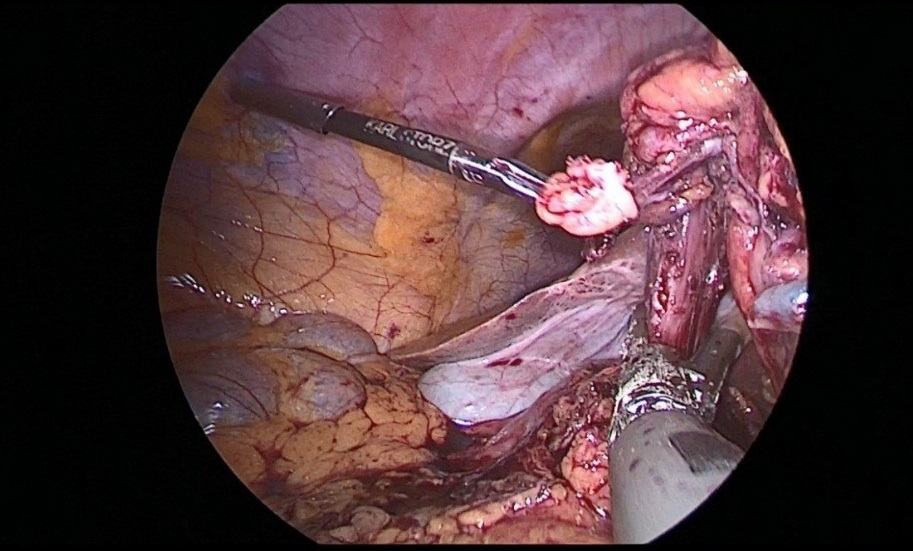

After crossing the pyloric sphincter, laparoscopic lymph node dissection of the VII, VIIIa, IX, XI, XIIa groups of lymph nodes was performed (Figure 9 a, b, c, d).

Figure 9a,b,c,d: Lymph node dissection of the hilum of the liver and celiac trunk.